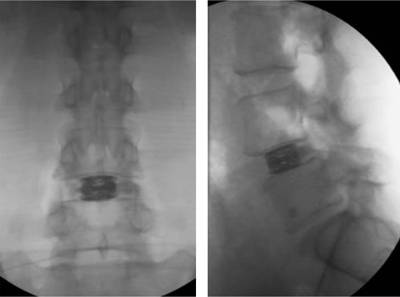

Post-operative radiologic control of the inserted expandable cage